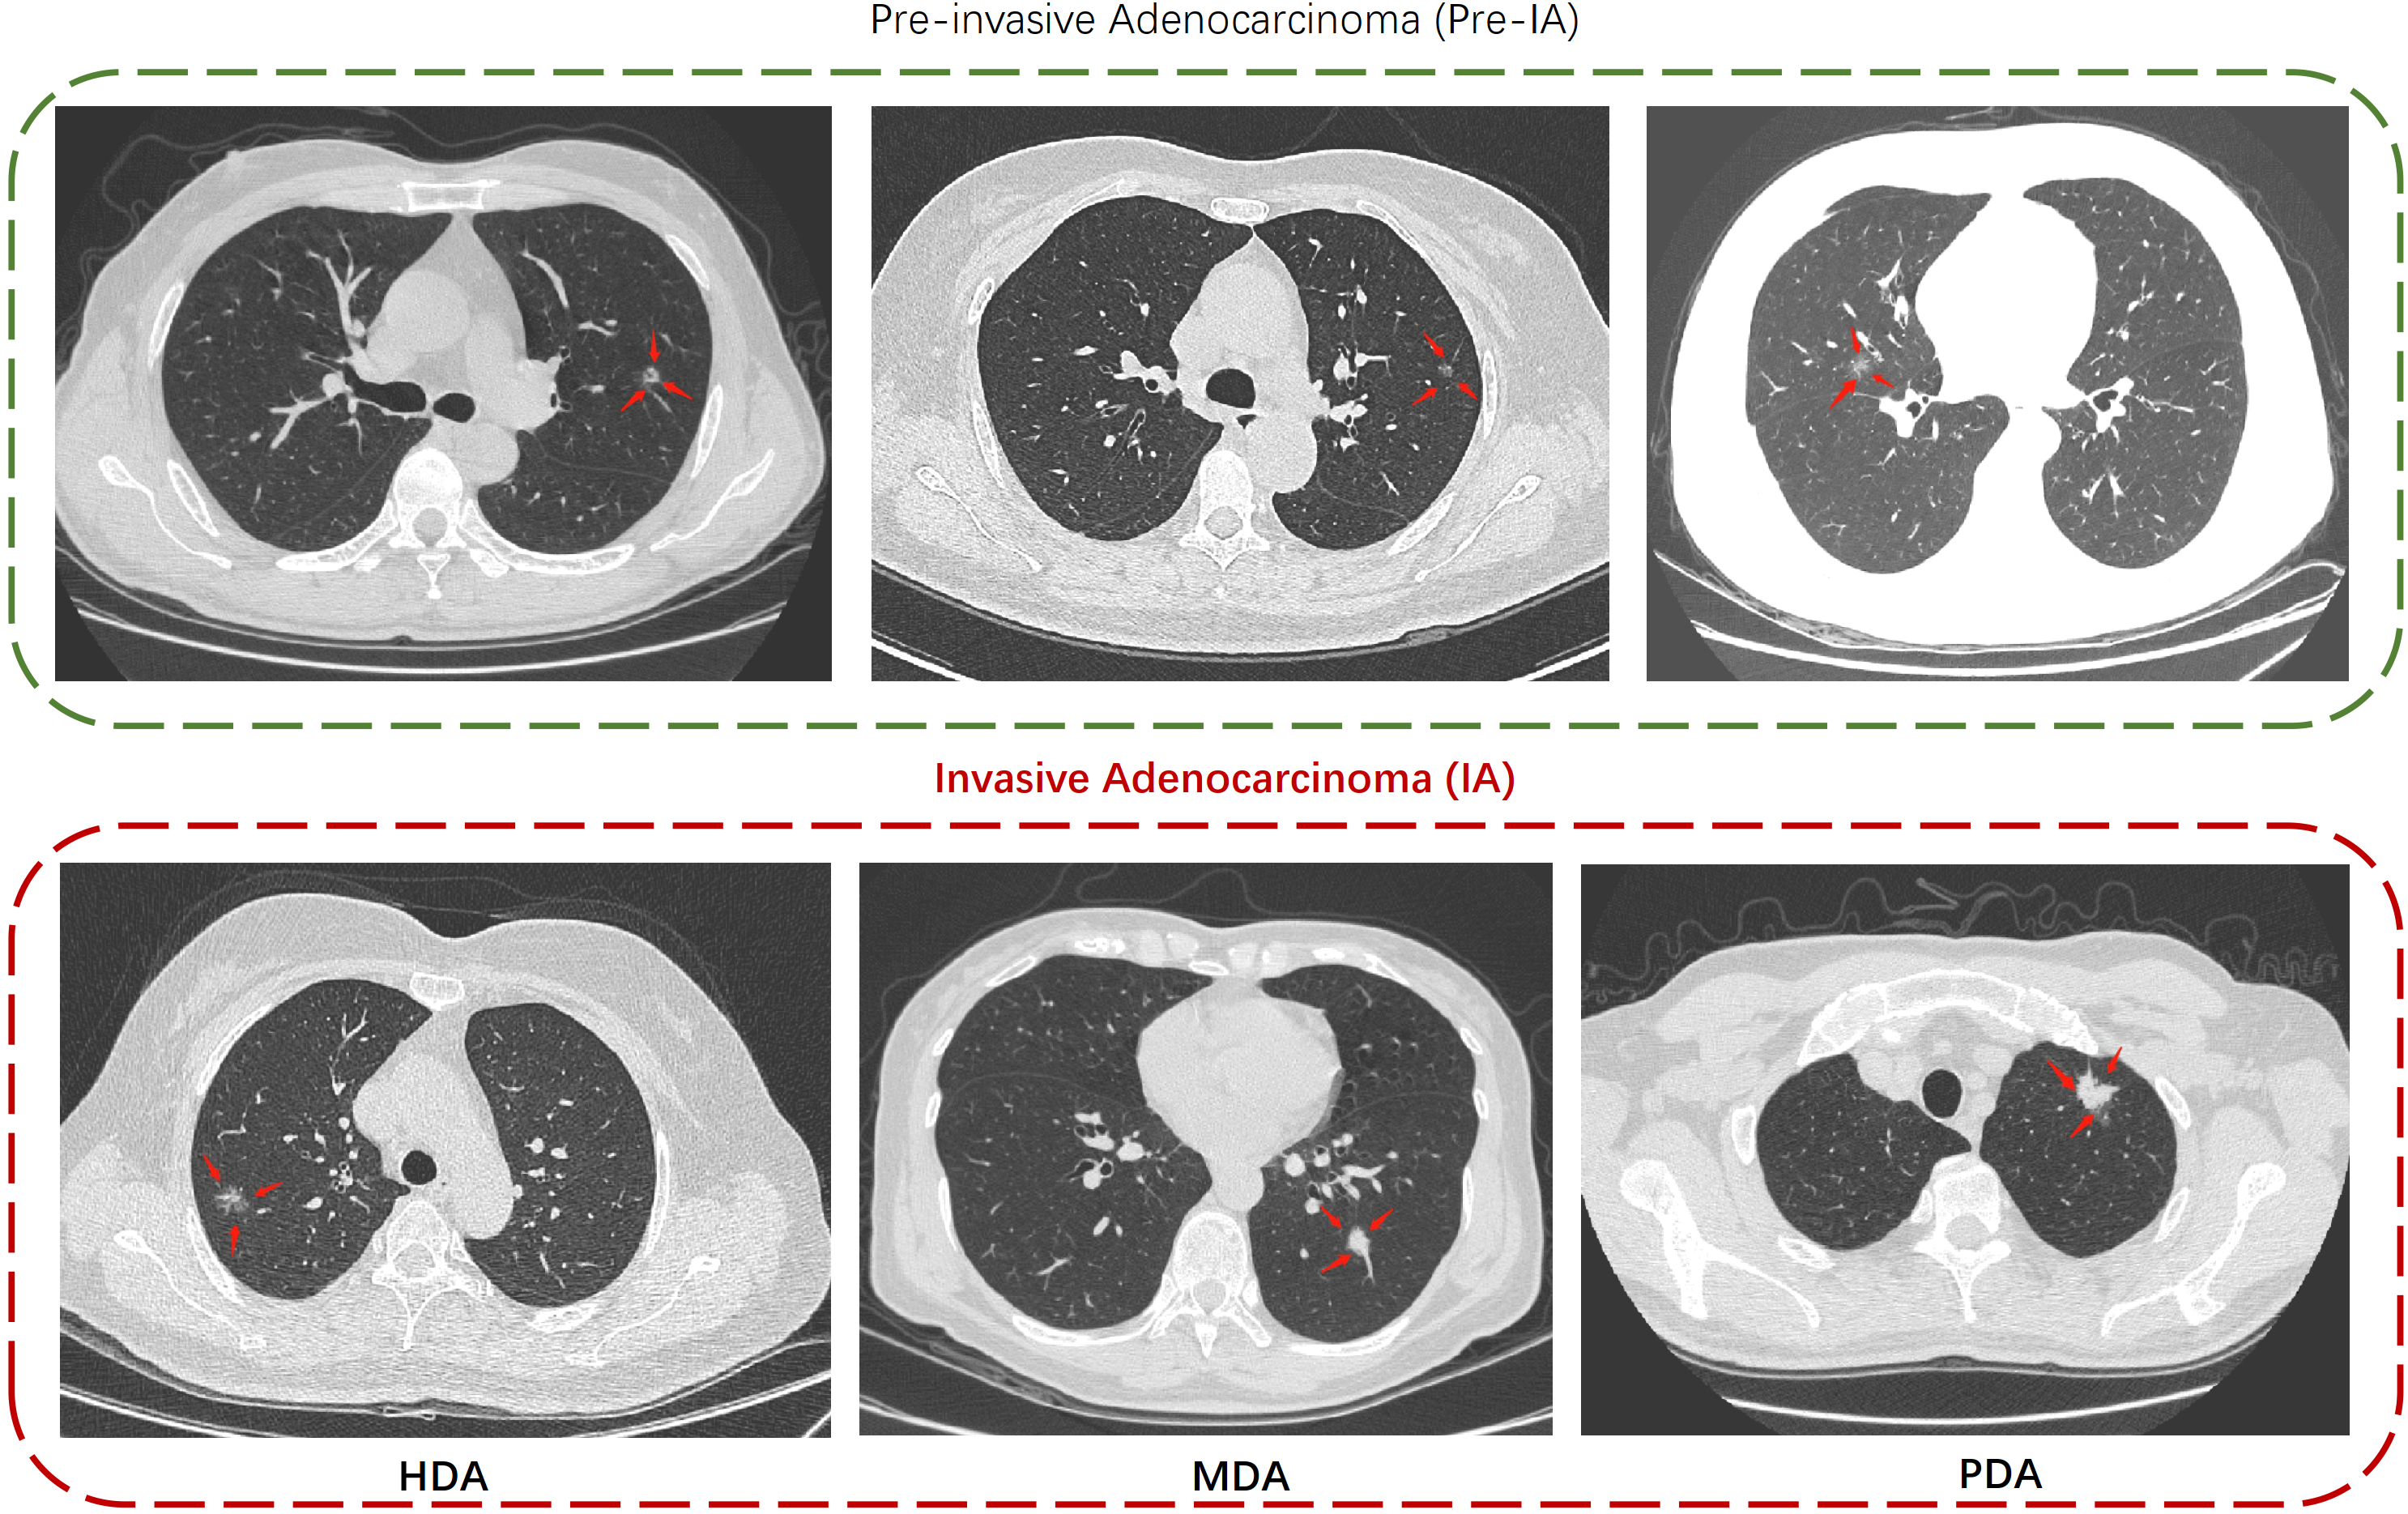

Figure 1: Illustrations of different subtypes of LUAD. The top panel shows some examples of Pre-IA, and the bottom panel shows the subtypes of IA. Specifically, recognizing the subtypes of IA would be helpful for determining an appropriate surgical model [9].

According to the International Association for the Study of Lung Cancer classification, LUAD can be divided into two categories according to their pathological results (see Fig.1): pre-invasive adenocarcinoma (Pre-IA) and invasive adenocarcinoma (IA). Pre-IA consists of atypical adenomatous hyperplasia, adenocarcinoma in situ, and minimally invasive adenocarcinoma. IAs can be further divided into three subtypes according to the morphology of the cancer cells [10]: highly-differentiated adenocarcinoma (HDA), moderately-differentiated adenocarcinoma (MDA), and poorly-differentiated adenocarcinoma (PDA). In clinical practice, Pre-IAs only require regular follow-up care, while IAs should receive immediate treatment with appropriate lung cancer resection (such as lobectomy for MDA or PDA and sublobar resection for HDA). Therefore, distinguishing IAs from Pre-IAs and further predicting the subtypes of IAs using CT images would be meaningful, as this could facilitate planning a more reasonable surgical treatment prior to the operation [9]. Although many attempts have been made to develop techniques for automatic Pre-IA/IA classification of pulmonary nodules [5, 4, 7], to the best of our knowledge, no techniques for subtype classifications of IAs have been published to date. We considered that it would be highly valuable to investigate whether the various subtypes of IA could be accurately classified through screening CT scans.

The proposed method can not only distinguish IAs from Pre-IAs, but can also distinguish different subtypes of IAs. This task is complicated by the fact that pulmonary nodules exhibit both intra-class similarity and variances in size, brightness, shape, and even in the composition of the surrounding tissue (as depicted in Figure 1). This can complicate the training process and make it challenging to obtain distinguishing characteristics specific to the lesion. We proposed an adaptive feature fusion architecture to leverage both radiomics and deep semantic features. The architecture of the proposed method is shown in Fig. 2. Specifically, we develop a multi-head attentional feature fusion module (MHA-FF, module C) to aggregate both radiomics and deep features, where radiomics features are extracted by a knowledge-driven module (i.e., module A) and deep features are obtained by a data-driven module (i.e., module B). Our contributions can be summarized as follows: I) We proposed the MHA-FF, a novel module for integrating radiomics features and deep features. It has the ability to interpret attention-based discriminative features. II) For effective extraction of radiomics features, we combined the use of a lung mask and a multi-scale nodule mask during extraction. This enabled us to consider not only nodule-related information, but also lung-related information. III) We performed extensive experiments on a real-world dataset collected from a multicenter cohort to demonstrate the superiority of the proposed approach over current state-of-the-art solutions.